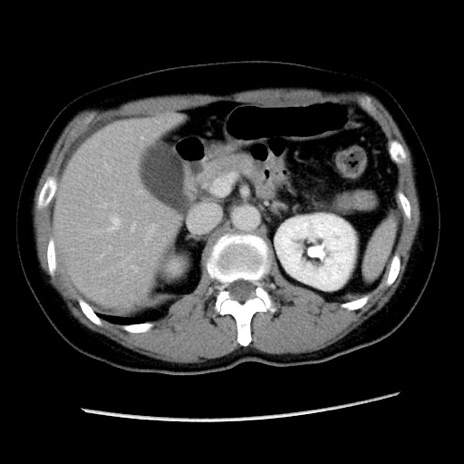

症例10(横断像)

【症例】 50歳代女性

【主訴】 腹痛

【現病歴】前日生レバーを食べた。今朝に排便あり。 昼前に突然発症の腹痛を生じ、当院救急外来を受診した。

【既往歴】 子宮筋腫にてで子宮全摘後

【身体所見】 意識清明、腹部:平坦、軟、下腹部やや左を中心に圧痛・反跳痛あり、筋性防御あり

【データ】WBC 7800、CRP 0.07